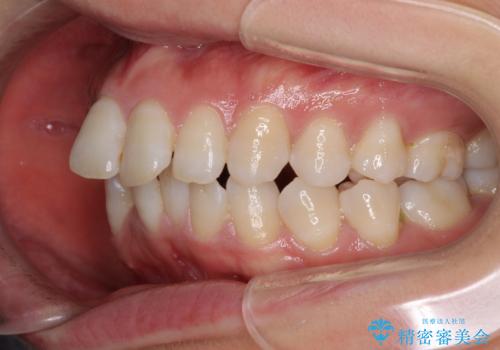

- 上の前歯の飛び出した感じと上下前歯のデコボコを気にして来院された患者様です。

叢生が強く、口元の突出感もあるため、上顎左右第一小臼歯4本を抜歯することとしました。

2年ほどインビザラインを使用しましたが、どうしても歯の移動がマウスピースに追随せず、全顎ワイヤー矯正へ切り替えました。

ワイヤー装着後は2年弱で、しっかりと仕上げることができました。